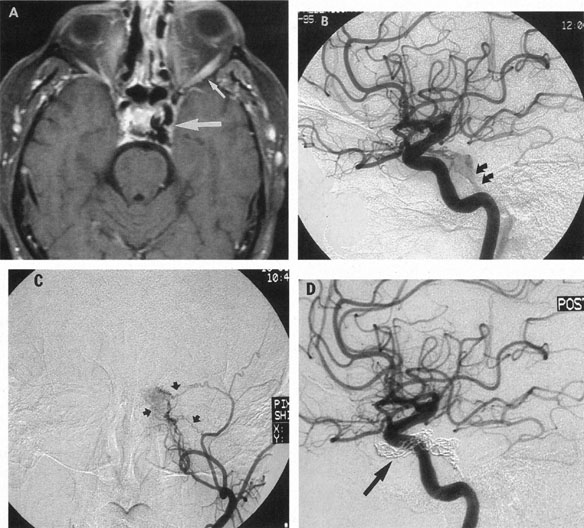

The therapy for AVMs has been reviewed elsewhere.91–93 The preferred treatment remains complete surgical excision of the malformation. However, significant advances in endovascular and radiosurgical techniques have resulted in a marked increase in the use of multimodal, staged approaches to AVM treatment. A variety of intravascular techniques use embolization91 with materials such as particles of polyvinyl alcohol (PVA), platinum coils, and injection of liquid N-butyl-cyanoacrylate (NBCA) adhesive (Fig. 11). Complications of intravascular embolotherapy include vessel perforation by the catheter, migration of embolic materials, and infarction and hemorrhage of normal brain.

Fig. 11. Embolization of middle cerebral vessels that supply occipital lobe arteriovenous malformation (AVM). The patient had a subarachnoid and intraparenchymal hemorrhage that produced a left homonymous field defect. A: Right carotid arteriogram demonstrates contribution via posterior communicating artery to a right occipital lobe AVM. B: Vertebral injection. The arrow points to the enlarged right posterior cerebral artery that is a major feeder of the AVM. C: Right carotid arteriogram during glue embolization procedure. The arrow points to a catheter as it traverses the segment seen in (B). The catheter was advanced via the internal carotid artery but is positioned far posteriorly. D: Upper branches to the AVM now are occluded, with residual low-flow vascularization via the middle cerebral artery. E: Skull film showing radiopaque glue within the AVM and blood vessels previously supplying it. The patient had a persistent visual field defect but greatly reduced headache and no persistence of subjective bruit. (Courtesy of Dr. Joseph Horton.)